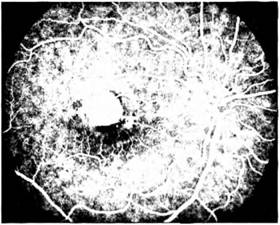

Мал. 1.30. ФАГ. Центральний xopope- тиніт

Флюоресцентна ангіографія (ФАГ), запропонована в 1961 p. Novotny і Alvis, є цінною методикою прижиттєвого дослідження судин очного дна. Вона слугує необхідним доповненням до основних клінічних методів дослідження, даючи значний обсяг інформації для діагностики й лікування патологічних станів сітківки і зорового нерва.

Ця методика ґрунтується на здатності флюоресцеїну поглинати синє світло і випромінювати жовто-зелене за нормального значення pH крові (7,37—7,45). Флюоресцеїн нетоксичний і безпечний для більшості пацієнтів. У разі надходження його в кров відбувається поетапне контрастування судин, що можна зафіксувати фотографічно. Для цієї мети використовують різні моделі фундус-камер з

високою швидкістю фотографування (наприклад, фундус-камеру F450 фірми «Zeiss»). Контрастовані флю- оресцеїном судини на позитивних фотознімках мають вигляд світлих смут на тлі очного дна, на негативах спостерігають протилежну картину.

Дослідження проводять у такий спосіб: до введення флюоресцеїну роблять кілька фотографій без фільтра, далі в синьому світлі виконують контрольний знімок. Після цього швидко вводять флюоресцеїн (5,0 мл 10% розчину флюоресцеїн-натрію) у ліктьову вену і через 5—7 c почина-